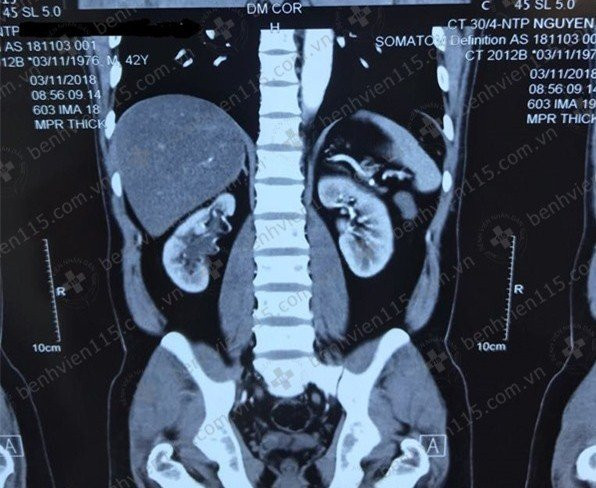

| Hình ảnh thận phải ứ nước do hẹp khúc nối bể thận - niệu quản trên phim chụp cắt lớp vi tính. Ảnh: BSCC |